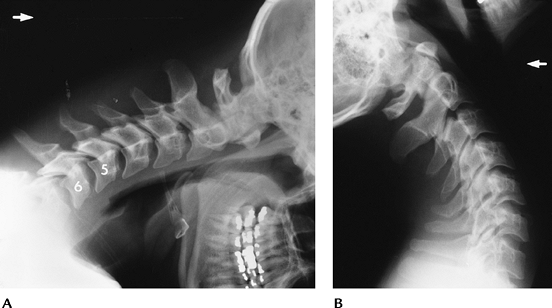

![]() |

FIGURE 3-22 Flexion distraction injury with posterior ligament tear at C5–C6. Flexion (A) and extension (B)

views show subluxation and widening of the interspinous distance and facet joints with flexion that reduces with extension. Treatment-posterior fusion. |

FIGURE 3-23 Unilateral locked facet. (A) AP radiograph shows disc space asymmetry (arrow) at C4–C5 and rotation of the spinous process. (B) Lateral view shows subluxation, and the C4 facets form the “bow-tie” sign. (C) Oblique view shows the facet overlap (arrow).

|

FIGURE 3-24 Sagittally reformatted CT images of locked (A) and perched (B) facets (arrow).